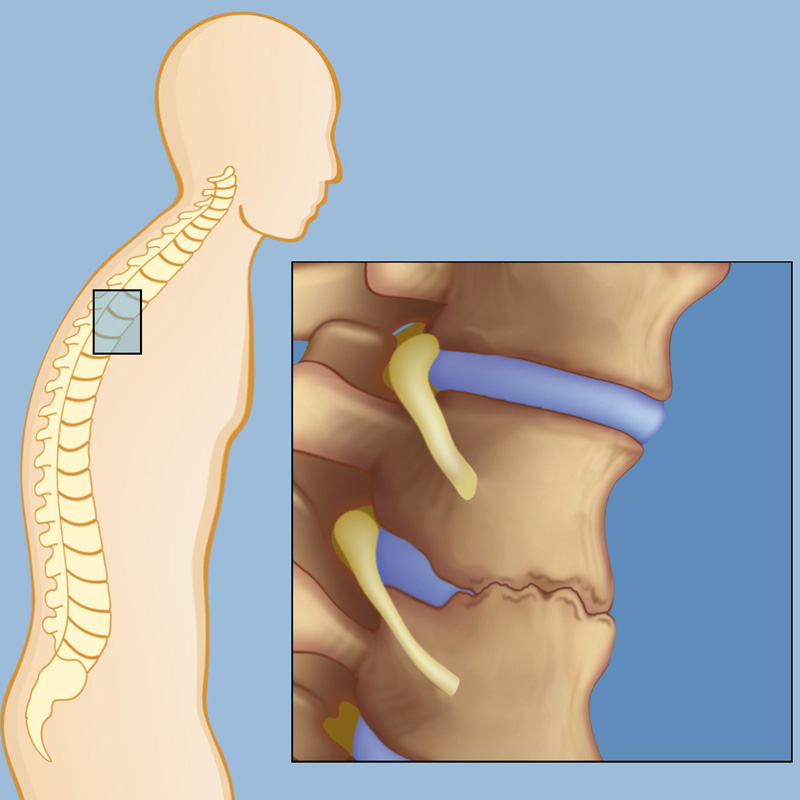

Over time, ongoing inflammation can lead to new bone formation between the vertebrae, causing parts of the spine to fuse. This may result in reduced flexibility and, in more advanced cases, a forward-stooped posture.

- Postural changes – In advanced cases, new bone formation between vertebrae may cause the spine to stiffen and lead to a forward-stooped posture.